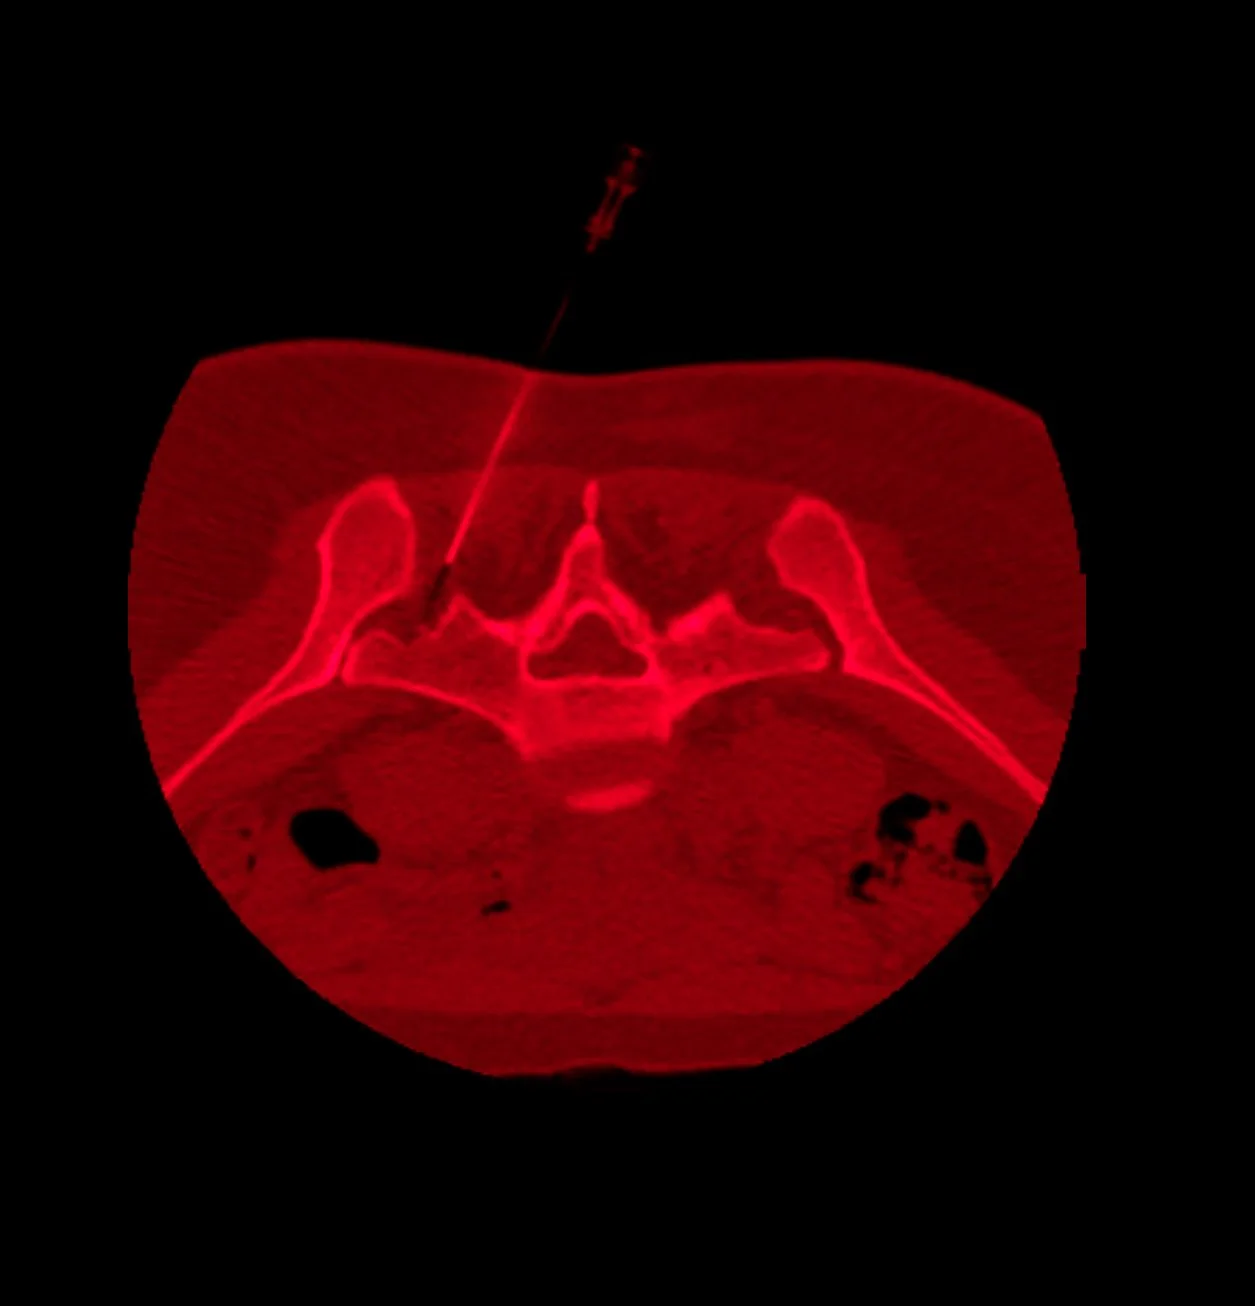

Confessions of a Bad-Backed Young Masc

Click each image to reveal its text.

Click each image to reveal its text.